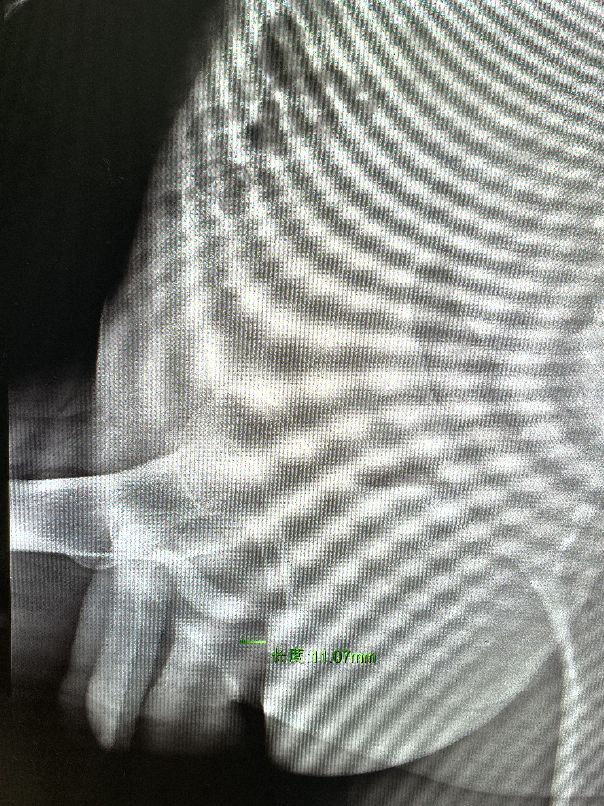

果不其然,小翟的这个选择是非常明智的。入院后排泄性膀胱尿道造影显示球部尿道狭窄1厘米左右(图一),今天在硬腰麻醉小,我给他做了独创性新手术。术中发现球部尿道狭窄1厘米,在1~5点位有一个5毫米大小的瓣膜样物堵塞尿道(图二),再怎么扩张尿道也无济于事。我们用专利器械小、中、大三种尿道内切开镜次第将狭窄尿道切开,至F26镜子顺利通过,然后电切瓣膜样物,完全理顺尿道。术毕留置F22导尿管。手术全程20分钟,出血量1毫升,令人不敢相信。从手术过程看,我们可以肯定不会发生阳痿、感染等严重并发症,一个月后扩张尿道四次并康复治疗即可治愈。我们对他感叹到:你这是非常明智的选择。而且没有多次手术失败,我们做起独创性新手术也轻松愉快。

图一 术前排泄性膀胱尿道造影显示球部尿道狭窄